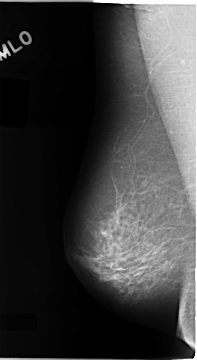

C_0108_1.LEFT_MLO

LEFT_MLO LINES 4760 PIXELS_PER_LINE 2656 BITS_PER_PIXEL 12 RESOLUTION 50 OVERLAY